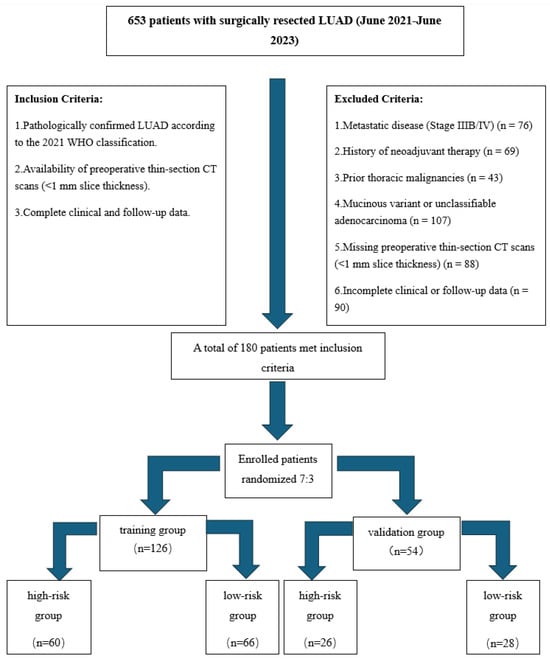

A Clinical–Radiomics Nomogram for the Preoperative Prediction of Aggressive Micropapillary and a Solid Pattern in Lung Adenocarcinoma

by

Xiangyu Xie, Lei Chen, Kun Li, Liang Shi, Lei Zhang and Liang Zheng

Curr. Oncol. 2025, 32(6), 323; https://doi.org/10.3390/curroncol32060323 - 30 May 2025

Background: A micropapillary pattern (MP) and solid pattern (SP) in lung adenocarcinoma (LUAD), a major subtype of non-small-cell lung cancer (NSCLC), are associated with a poor prognosis and necessitate accurate preoperative identification. This study aimed to develop and validate a predictive model combining

[...] Read more.

Background: A micropapillary pattern (MP) and solid pattern (SP) in lung adenocarcinoma (LUAD), a major subtype of non-small-cell lung cancer (NSCLC), are associated with a poor prognosis and necessitate accurate preoperative identification. This study aimed to develop and validate a predictive model combining clinical and radiomics features for differentiating a high-risk MP/SP in LUAD. Methods: This retrospective study analyzed 180 surgically confirmed NSCLC patients (Stages I–IIIA), randomly divided into training (70%, n = 126) and validation (30%, n = 54) cohorts. Three prediction models were constructed: (1) a clinical model based on independent clinical and CT morphological features (e.g., nodule size, lobulation, spiculation, pleural indentation, and vascular abnormalities), (2) a radiomics model utilizing LASSO-selected features extracted using 3D Slicer, and (3) a comprehensive model integrating both clinical and radiomics data. Results: The clinical model yielded AUCs of 0.7975 (training) and 0.8462 (validation). The radiomics model showed superior performance with AUCs of 0.8896 and 0.8901, respectively. The comprehensive model achieved the highest diagnostic accuracy, with training and validation AUCs of 0.9186 and 0.9396, respectively (DeLong test, p < 0.05). Decision curve analysis demonstrated the enhanced clinical utility of the combined approach. Conclusions: Integrating clinical and radiomics features significantly improves the preoperative identification of aggressive NSCLC patterns. The comprehensive model offers a promising tool for guiding surgical and adjuvant therapy decisions.

Full article

(This article belongs to the Special Issue Artificial Intelligence in Thoracic Surgery)

►▼

Show Figures

Figure 1